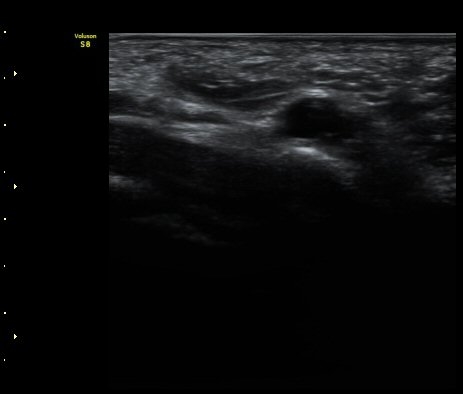

ÃÊÀ½ÆÄ °Ë»ç

¤º